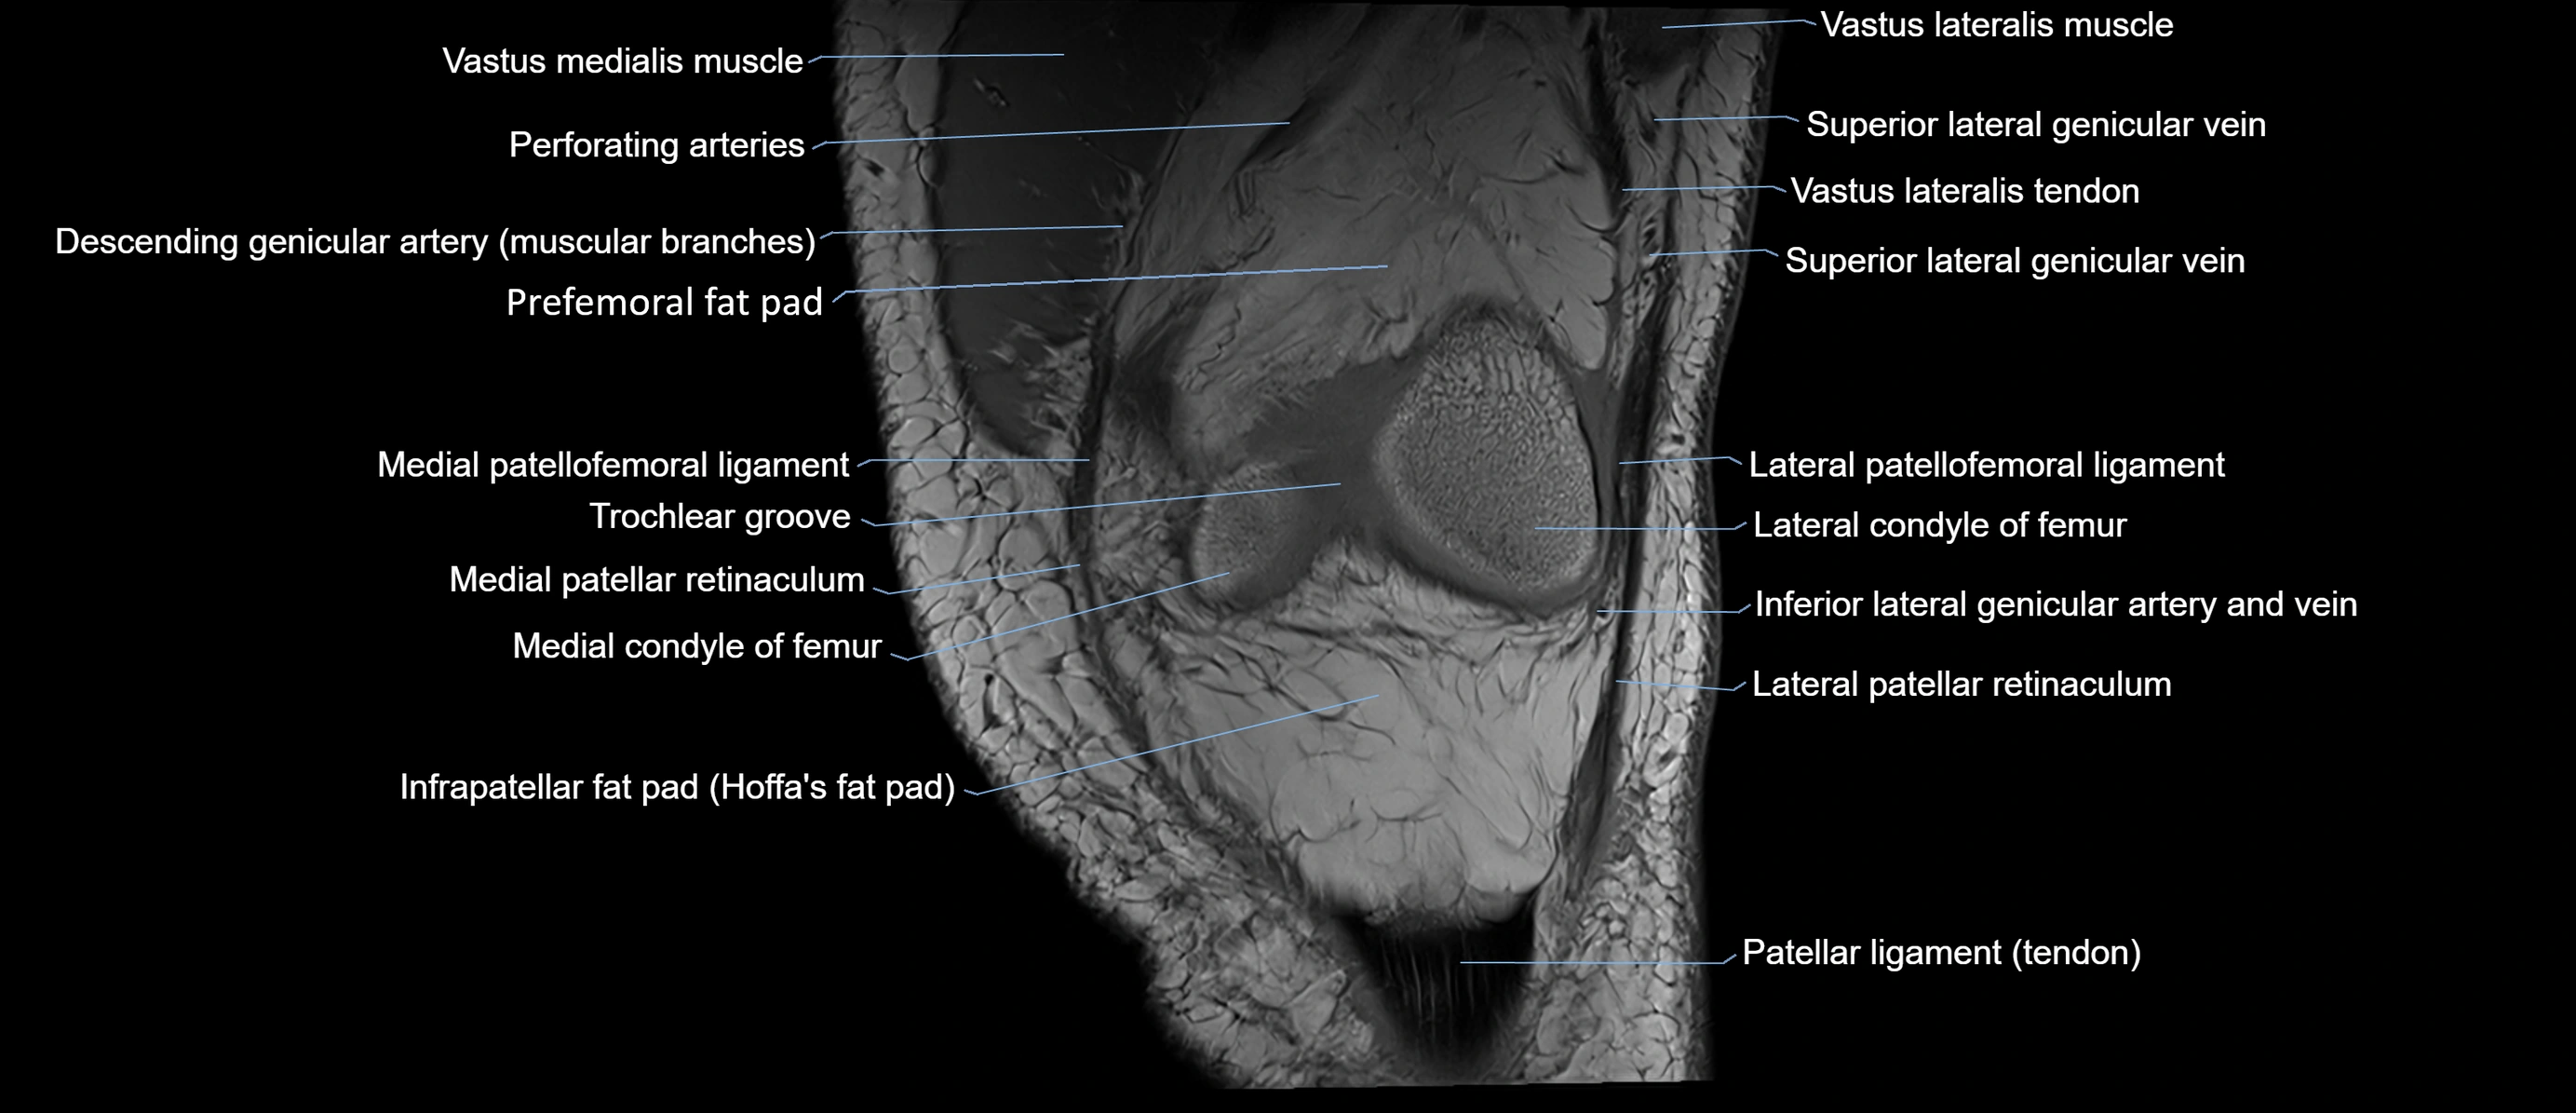

- Knee Joint